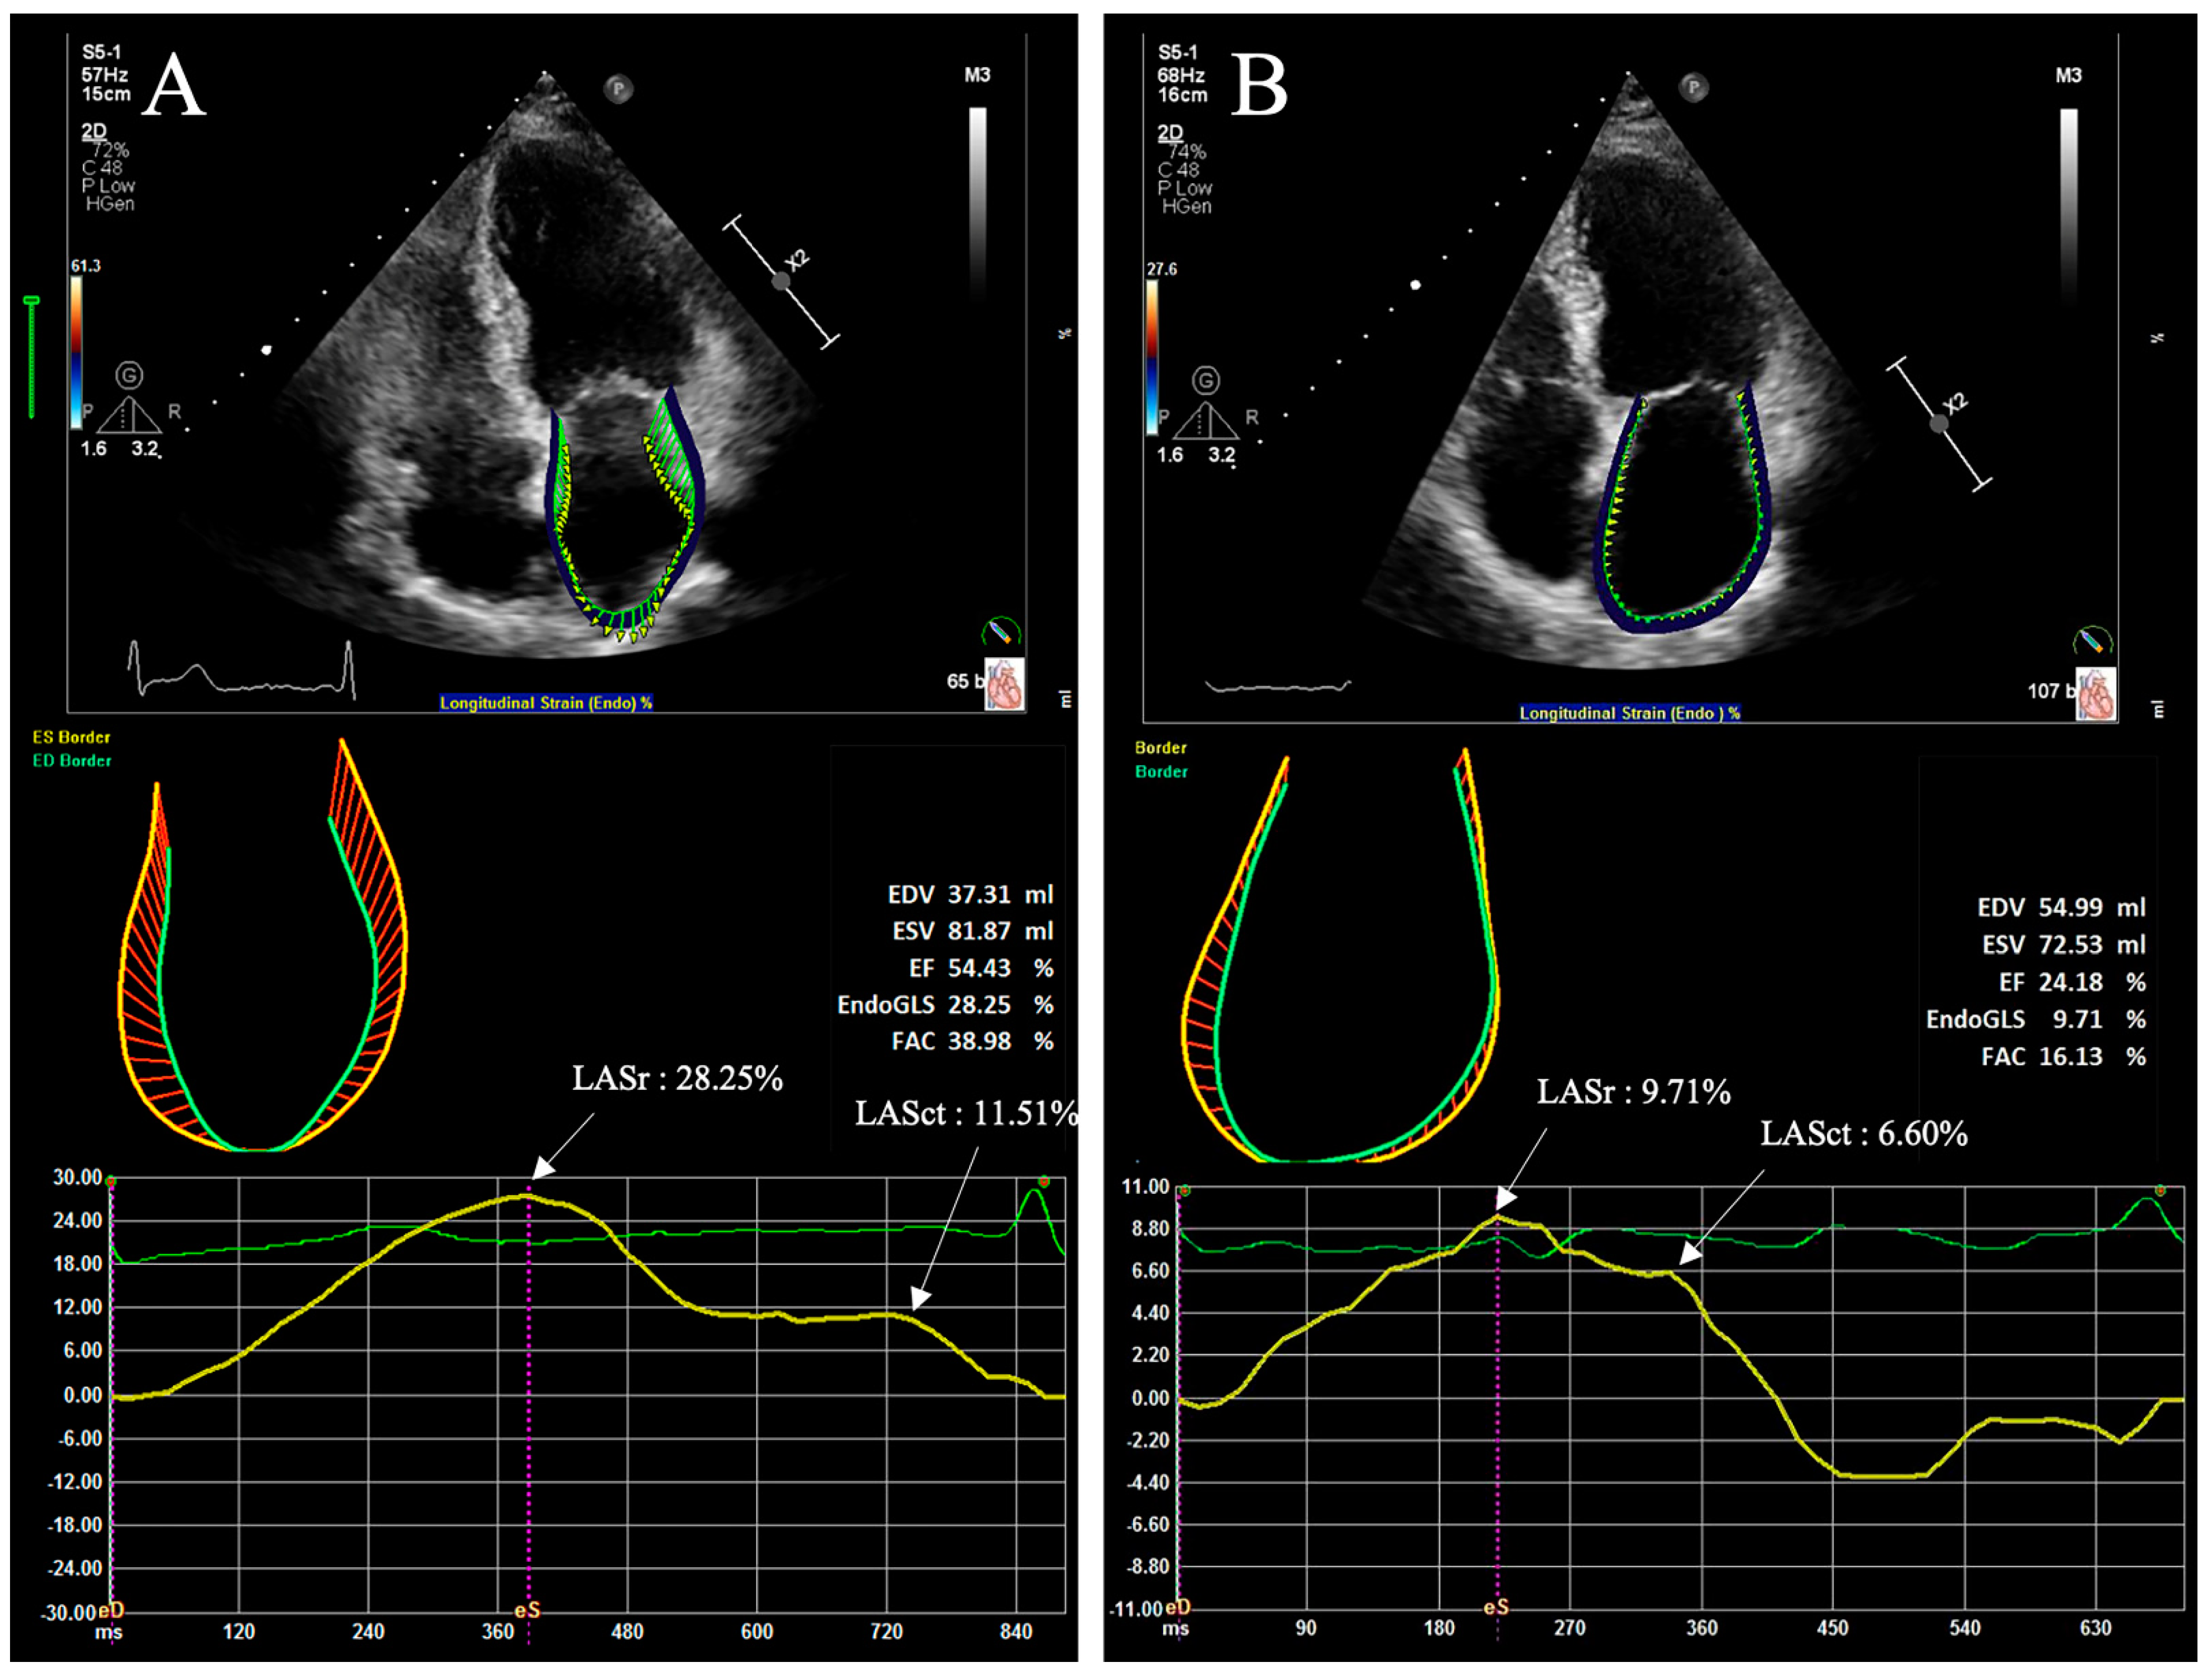

3.2.1. Two-Dimensional Speckle Tracking Echocardiography

| LASr (PALS) | Peak left atrium global longitudinal strain during reservoir phase (peak left atrium longitudinal strain) | The difference of the strain value at mitral valve opening minus ventricular end-diastole (the peak value of longitudinal strain during LV systole) |

| LASct (PACS) | Peak left atrium global longitudinal strain during contraction phase (peak left atrial contractile strain) | The difference of the strain value at the ventricular end-diastole minus onset of atrial contraction (the value of strain at the onset of P-wave in electrocardiogram) |

| LAScd | Peak left atrium global longitudinal strain during the conduit phase | The difference of the strain value at the onset of atrial contraction minus mitral valve opening (LASct minus LASr) |